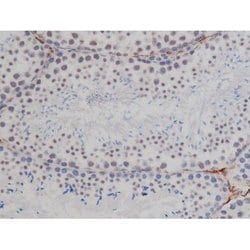

Invitrogen™ Phospho-NPM1 (Thr199) Polyclonal Antibody

Antibody detects endogenous levels of Nucleophosmin only when phosphorylated at Threonine 199.

| Applications | Immunohistochemistry (Paraffin), Western Blot, Immunocytochemistry |